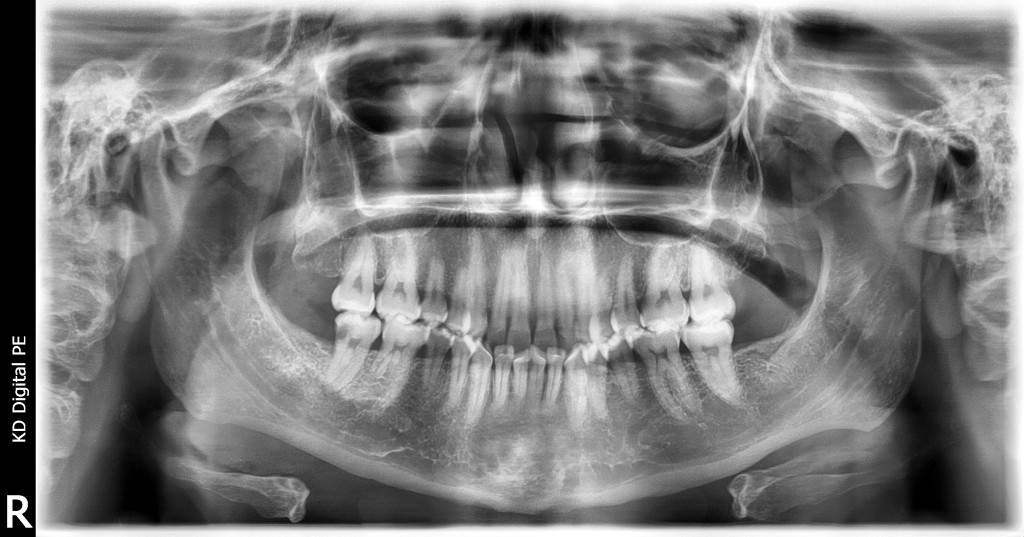

PANORÁMICA A BOCA CERRADA

• Te permite analizar la Interrelación Dental y Maxilar en Relación Céntrica.

• Realizar Valoración Ortodóntica y Cirugía.

• Realizar trazados Cefalométricos.